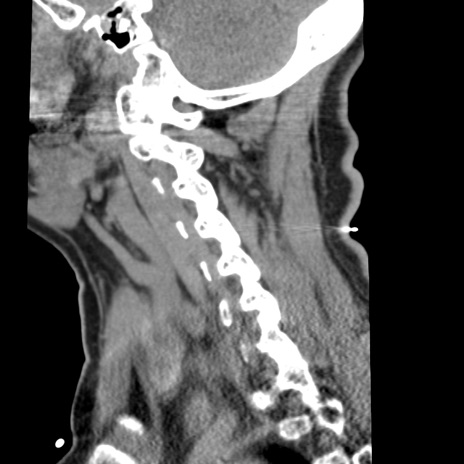

症例50 頚椎CT(矢状断像)

異常所見と診断は?

頚椎CT

冠状断像